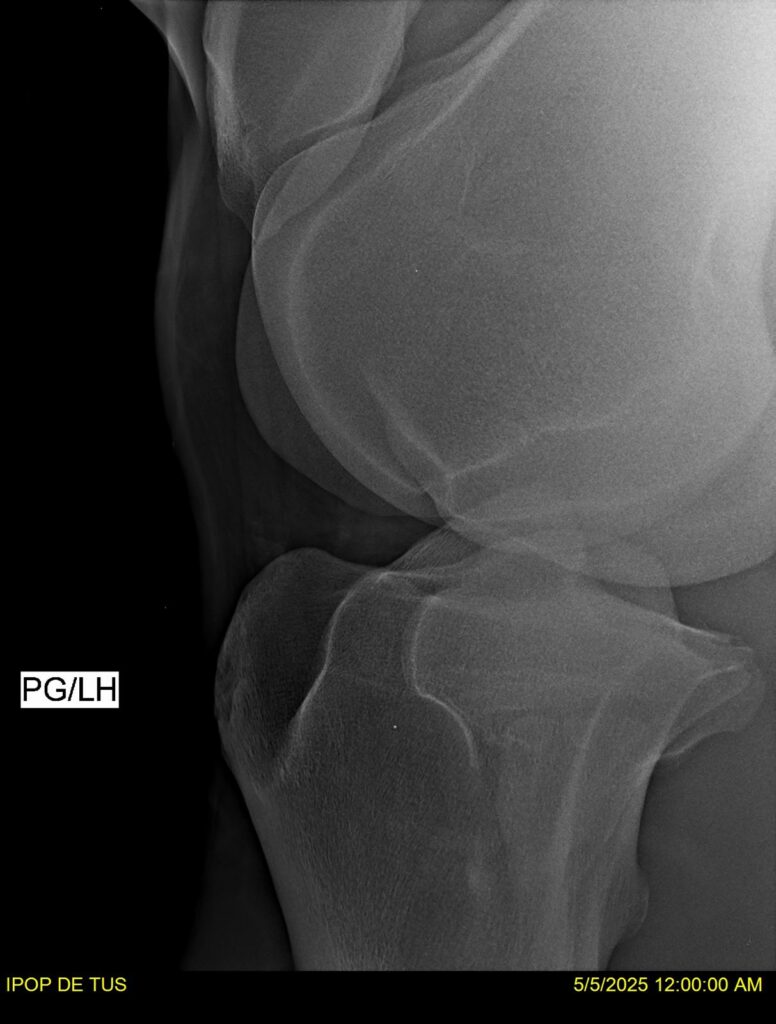

IPOP DE TUS, selle français, hongre, prendra 8 ans en 2026. LIFESTYLE x EROTICBLUS MONTOIS. Sans faute sur 125 et 130. Gentil cheval, respectueux avec des moyens et de la force. Transport OK, maréchalerie OK (pieds nus), santé RAS, Bilan clichés radios + clinique OK.

RADIOS ET CLINIQUE